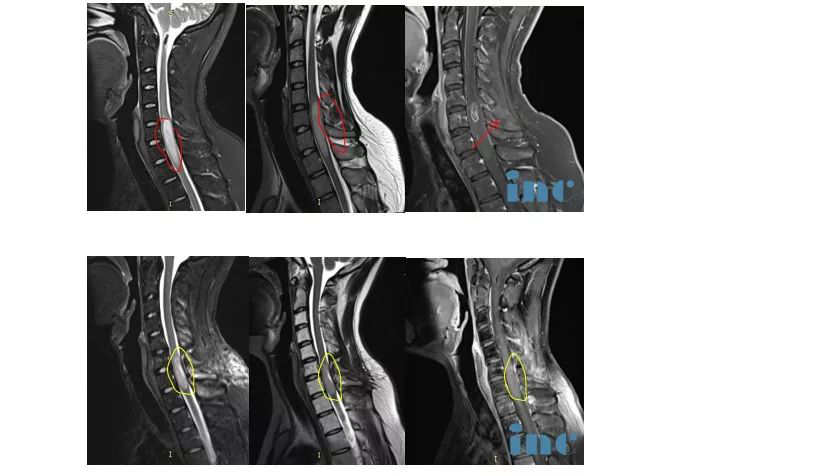

于是林先生奔赴德國,由巴教授為其行髓內(nèi)占位全切術(shù),頸5-6椎體成行術(shù),手術(shù)成功。關(guān)于這臺手術(shù),林先生還特意強(qiáng)調(diào):術(shù)后很快我就去做了核磁檢查,和術(shù)前對比明顯,這是“外行”都能看得見的切除效果。

手術(shù)前后影像對比

林先生在術(shù)后4天可以下地走路了,術(shù)后10天就出院回國接受后續(xù)治療了,根據(jù)林先生的反饋,現(xiàn)在頸部疼痛和手臂麻木程度減輕了不少,定期復(fù)查結(jié)果顯示他的脊髓腫瘤沒有增長和復(fù)發(fā),感謝巴教授,也慶幸自己當(dāng)初做的出國手術(shù)決定。